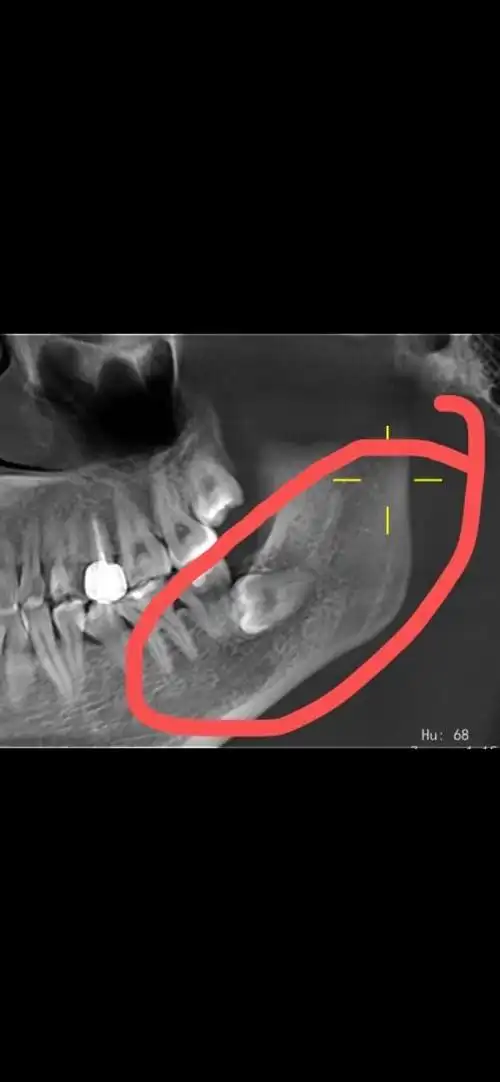

济南市口腔医院拔阻生智齿

问一下,这个横生智齿不疼也没啥影响,而且长的也挺大了,应该不会在长

好纠结!这种超低位横生智齿能拔吗?

横生的智齿一定要拔除吗?

小智齿,大麻烦,到底该不该拔?